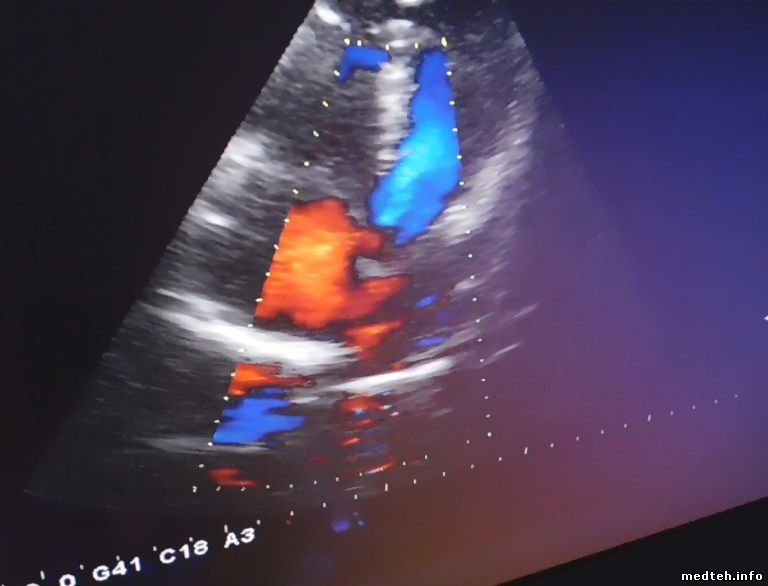

Добрый день!

Проблема похожая, на картинке с кардио датчиком идут помехи. Причём были эксперименты со сменой помещения, результат был положительный кратковременно. Датчик менялся на новый, но результат 0.

8345150.jpg (38.2 Kb)

Я не вижу на снимке помех. Возможно, они и есть, но на снимке их не видно.

К чему конкретно претензии? К В-картинке, или к доплеру? Уточните у врача, он вообще в курсе, что усиление доплера регулируется ручкой Flow Gain? Т.е. той крутилкой, которая под кнопкой включения доплера. Я встречал "врачей" (в ФМБА, кому интересно), которые не знали о существовании отдельной регулировки усиления доплера.

Чувствительность доплера я обычно проверяю руками. Ставлю окно на небольшую глубину, приближаю ладонь к датчику, но не касаюсь поверхности. Потом двигаю ладонью вверх-вниз, что бы расстояние от датчика менялось. Если доплер чует через воздух, значит чувствительность нормальная.